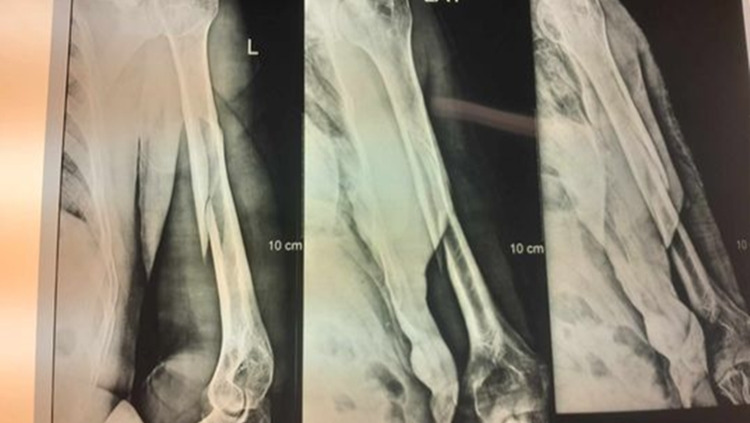

After his son David pulled him out of the water, we rushed him to the mainland. We want to extend a huge Thank You to Jerry Bodden for driving his boat at nighttime to get us there. X-rays in La Ceiba showed it to be a very bad break with some complications that most likely will require surgery. Edgar has made 2 trips to the mainland so far and has seen two different doctors.

The first doctor put a cast on his arm but then said he didn’t like the way it looked. After Edgar said he could still feel the bone grinding and moving which caused considerable pain and worry that something wasn’t right, he was recommended to a specialist who immediately cut the first cast off because it was done incorrectly, and put a new cast on which is the cast in the pictures.

Edgar’s next trip to La Ceiba to see the specialist on August 28th will be very important. If by a miracle he can avoid surgery, he will still have some additional medical expenses of around $1,180. If Edgar does need surgery on his arm for it to heal properly (it’s the bone that is slightly sticking out in the X-ray that’s causing the problem) then his medical expenses will be around $4,050. The surgery alone will be around $3,750.